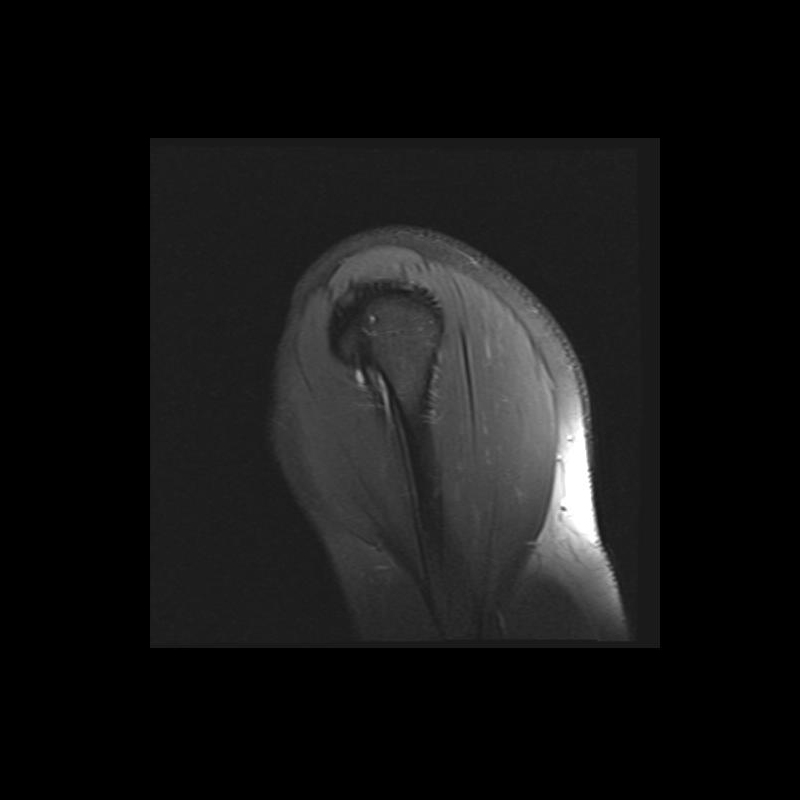

Shoulder MRI Anatomy